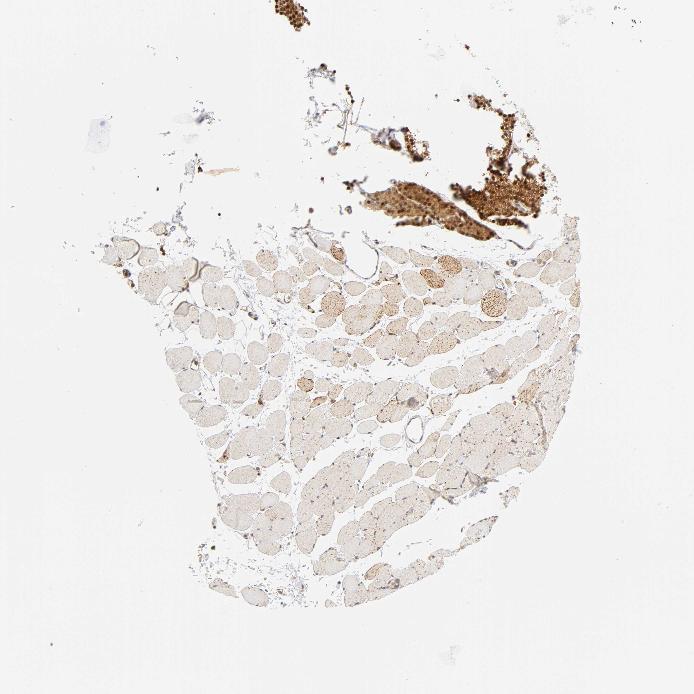

SKELETAL MUSCLE - Antibody stainingi

Antibody staining in the annotated cell types in the current human tissue is reported as not detected, low, medium, or high, based on conventional immunohistochemistry profiling in selected tissues. This score is based on the combination of the staining intensity and fraction of stained cells.

Each image is clickable and will lead to virtual microscopy that enables deeper exploration of all samples and also displays staining intensity scores, fraction scores and subcellular localization as well as patient and tissue information for each sample.

Antibody CAB004312

Myocytes Medium